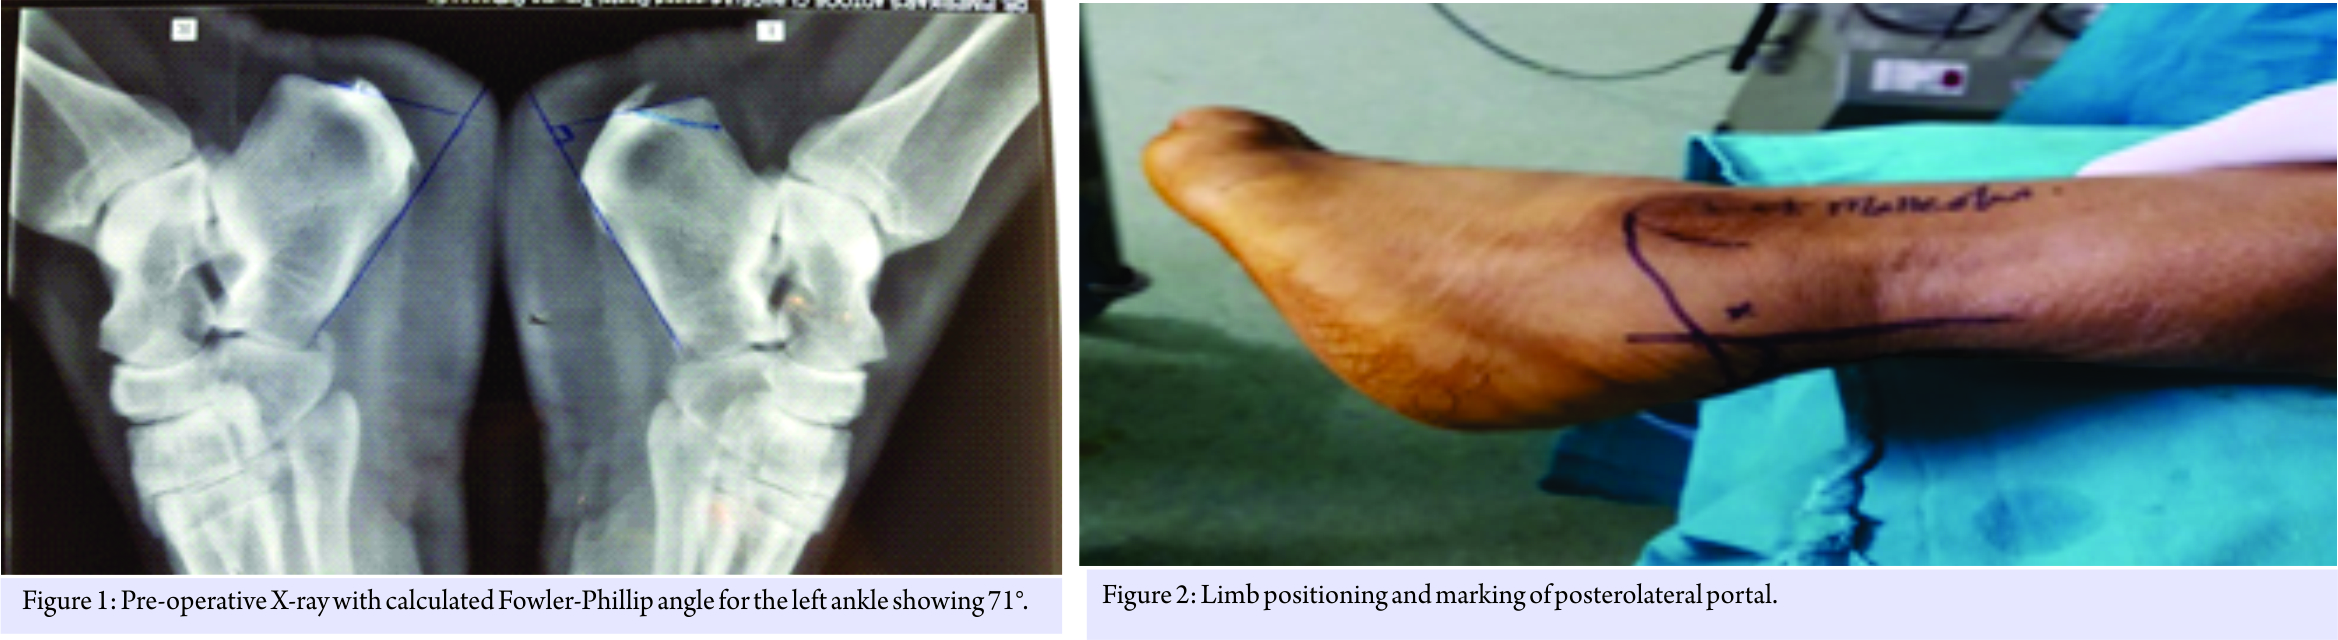

Case Report: The patient is middle-aged male aged 40 years, with higher basal metabolic index (BMI) and was diagnosed having a Haglund’s bump and was on conservative treatment for a period of over 6 months, with minimal relief. We did ECP with the patient in lateral decubitus position using two lateral portals instead of using one medial and one lateral portal, his American Orthopaedic Foot and Ankle Society score has improved from 64 to 98, and his Fowler-Philip angle is reduced from 71° to 45°.

The patient is a 40-year-old male patient with moderate obesity complaining of pain and swelling in the left retrocalcaneal region. X-ray and USG of ankle were taken and diagnosed having Haglund’s bump with retrocalcaneal bursitis, calcification in tendon is ruled out by USG. He was given 6 months of conservative treatment, but there was no improvement. His American Orthopaedic Foot and Ankle Society (AOFAS) score was 64 and Fowler- Philip angle is 71 (Fig. 1). Surgical intervention was planned. Surgical technique: The patient in spinal anesthesia is placed in lateral decubitus position. Tourniquet is placed in the thigh and the other limb is flexed at hip and knee so that it will not interfere with the procedure. The limb is scrubbed and draped, tourniquet inflated. Bony landmarks and the portals are marked.